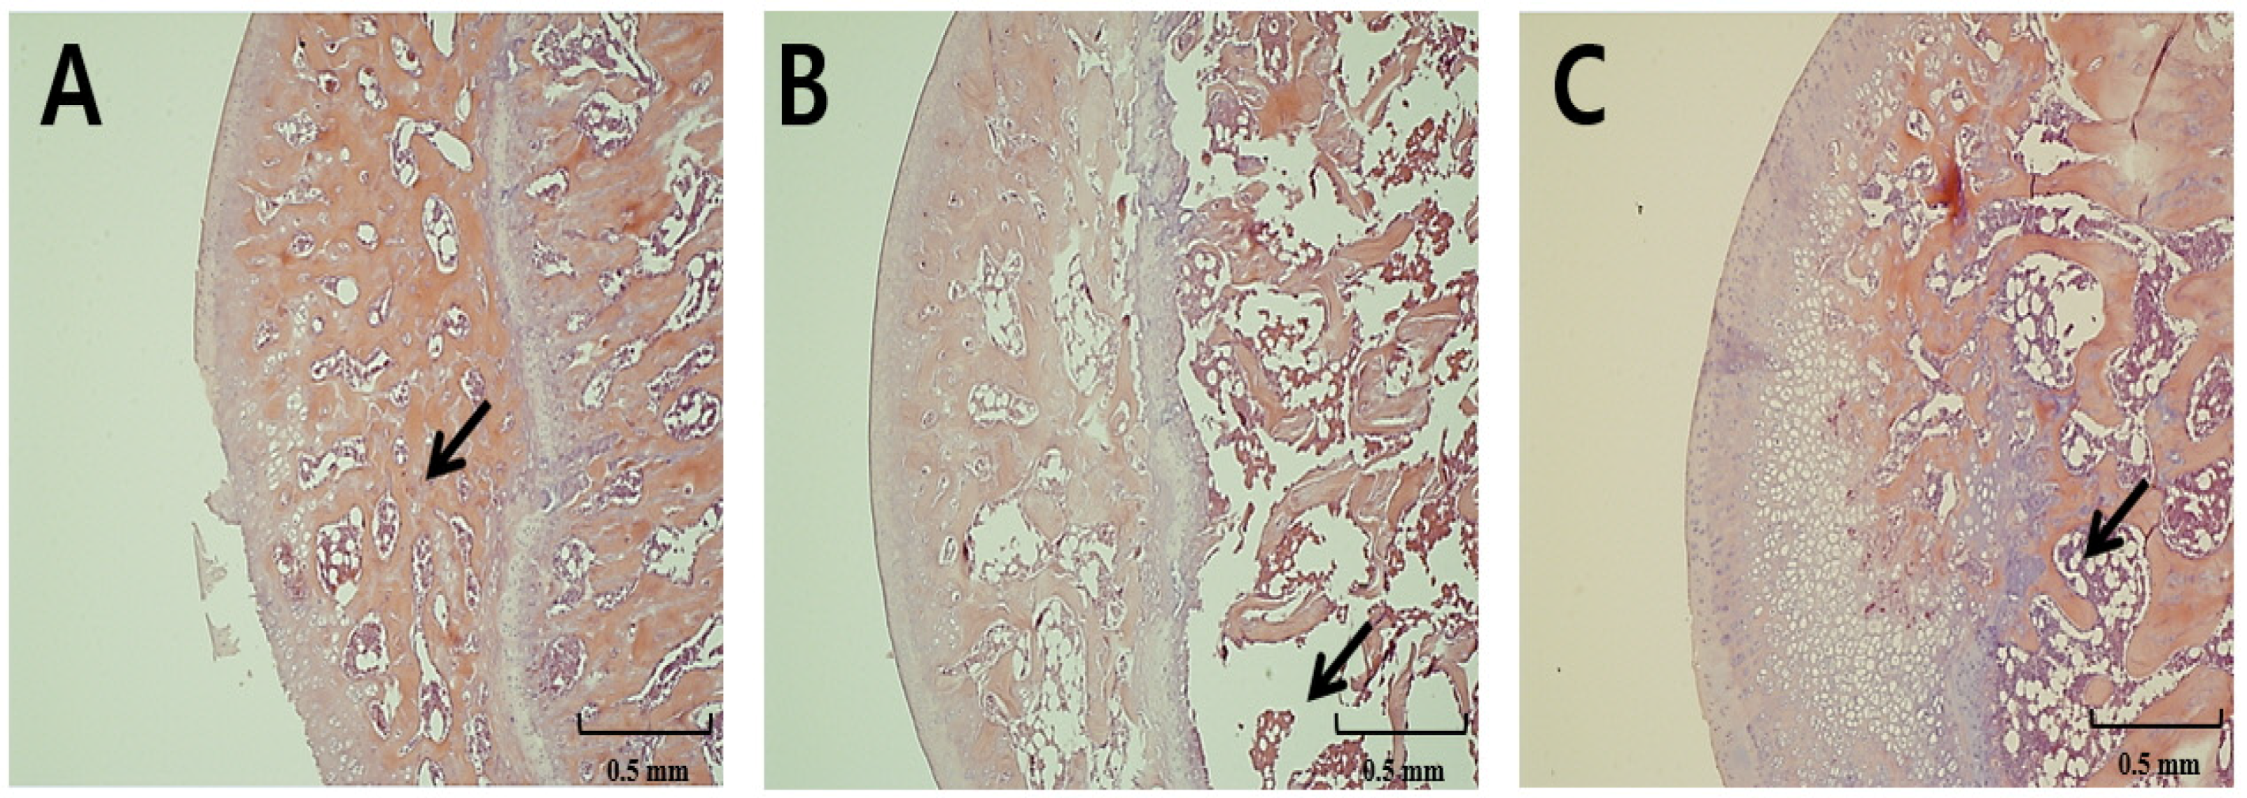

3.3. Light Micrographs of Right Femur